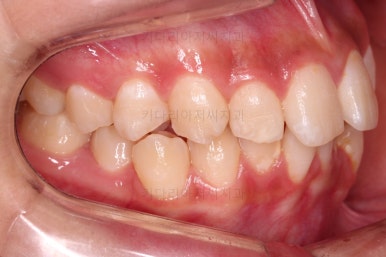

동래교정치과 초진 시의 입 안 모습이에요.

치열이 삐뚤고 덧니가 보이네요.

이번 환자분도 스스로는 보기 싫은 이유가 첫 번째였지만 사진에서도 보시다시피 양치가 잘 안되어 치석도 많고 잇몸도 부어있는 상태였어요.

그리고 앞니들이 마모가 많이 되어 있어서 각각의 치아들이 원래 형태에서 많이 변형된 것을 볼 수 있네요.